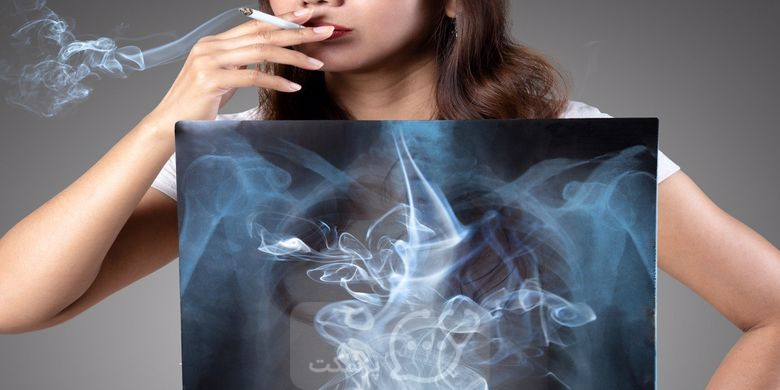

سیگار و خطر بروز بیماری ریه

سیگار بزرگترین تهدید برای سلامت ریه است. به غیر از سرطان، سیگار عامل اصلی آسیب به بافت های ریه و راه های هوایی است. در مورد ترک سیگار و هر تغییر دیگری که می توانید برای بهبود سلامت خود ایجاد کنید، با پزشک مشورت کنید. سیگار کشیدن یکی از بزرگترین خطرها برای عملکرد ریه است. ساختار و عملکرد ریه ها را تغییر ، تنفس را دشوار می کند و خطر ابتلا به بیماری های متعدد را افزایش می دهد.

ریه های سیگاری ها در مقابل ریه های سالم

سیگار کشیدن می تواند ظاهر فیزیکی ریه ها را تغییر دهد. آزمایشات تشخیصی، مانند اسکن CAT و اشعه ایکس قفسه سینه، احتمال دارد برخی از تغییرات را شناسایی کند. نمودار زیر برخی از تغییرات فیزیکی رایج را خلاصه می کند.

| ریه های سالم | ریه های سیگاری |

| رنگ صورتی | خاکستری یا سیاه |

| اندازه طبیعی | ریه های بزرگ شده |

| بدون التهاب | تکه های التهابی |

| دیافراگم گنبدی شکل | از دست دادن عضلات دیافراگم |

سیگار نه تنها باعث تغییرات فیزیکی می شود، بلکه عملکرد ریه ها را نیز تغییر می دهد. مدت زمانی که طول می کشد تا تغییرات ایجاد شوند در بین افراد متفاوت است.تغییرات باعث ایجاد علائم متعددی می شود که در تنفس طبیعی اختلال ایجاد می کند. به طور کلی، تفاوت بین ریه های یک فرد سیگاری و ریه های سالم شامل موارد زیر است :